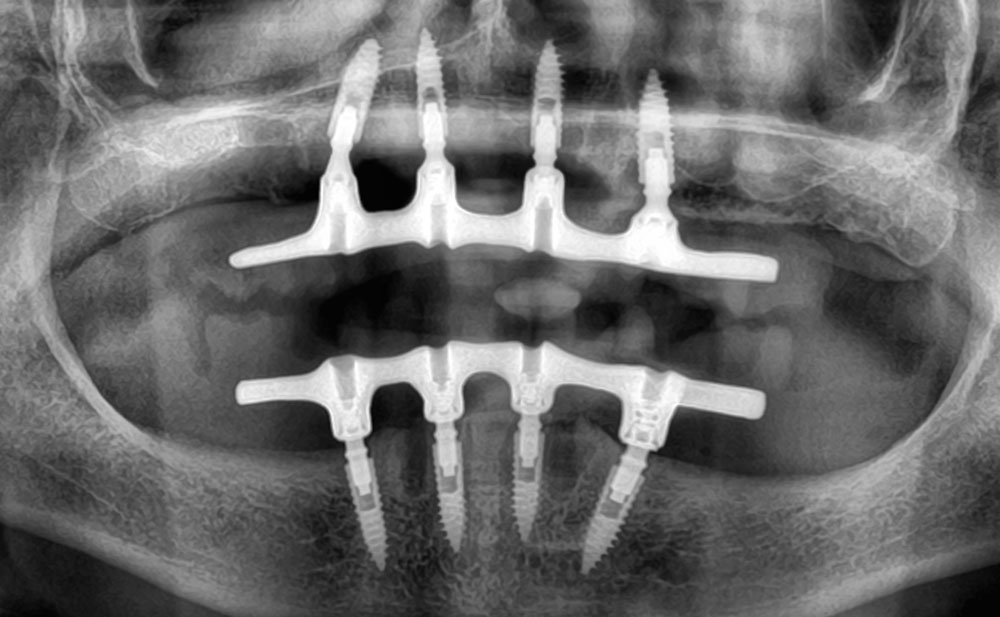

Rehabilitación con implantes All-on-Four

Antes

Planificación

Rehabilitación con implantes All-on-Five

Antes

Planificación